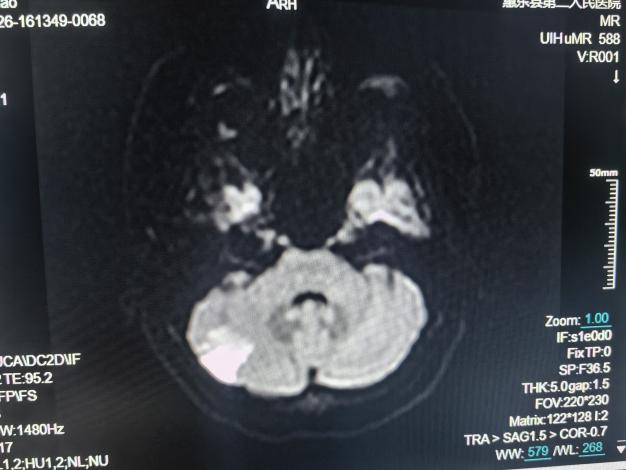

颅脑MRI检查

①先天性颅脑发育异常:包括器官源性畸形和组织源性畸形,MRI可确诊;②脑积水;③脑萎缩;④卒中及脑缺氧:脑梗塞和脑出血等;⑤脑血管疾病:高磁场的MR通过血管成像(MRA)技术显示;⑥颅内肿瘤和囊肿;⑦颅脑外伤;⑧颅内感染和其他炎性病变;⑨脑白质病。

急性脑梗死磁共振成像